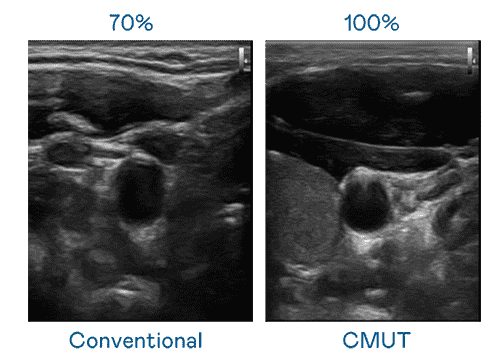

CMUT 技术是一种用电容式微机电元件来产生超音波讯号的技术。。。与传统 PZT 压电式技术相比,,,CMUT 频宽增加 30%,,更宽频的超音波讯号让影像解析度大幅提升,,是实现高影像品质医疗超音波扫描、、、促进精准医疗发展的关键技术。。。。

超音波影像的解析度高低,,首先取决于探头能发出的讯号频宽。。。。PA直营 CMUT 可提供高清晰的超音波讯号,,,,提供高频宽、、、高灵敏度、、、、影像纹理细节更高的超音波影像,,,,协助医护人员缩短影像判读时间及利用精准的医疗影像进行诊断。。。